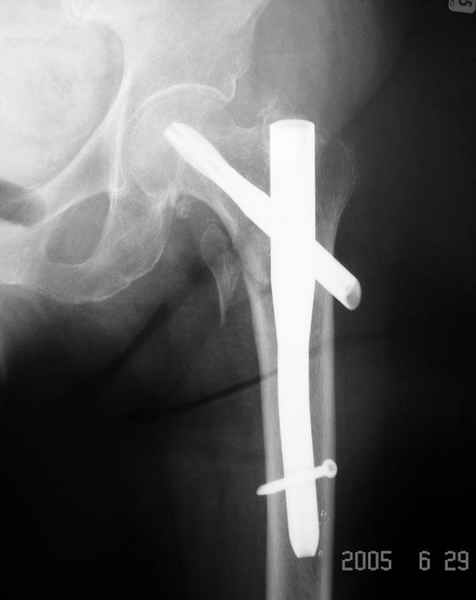

Дорогие коллеги,Как правильно определить такой перелом по классификации AO?

Как два отдельных или есть один соответствующий код? Фиксировать-то оба можно одним фиксатором...

Как раз недавно у меня был примерный случай: больному 36 лет, поступил ночью, травма в результате мотоциклетной аварии, кроме чрезвертельного и спирального перелома левого бедра имеется переломы костей предплечья с этой же стороны. Скелетное вытяжение, а на следующий день больной про оперирован на ортопедическом столе с дистракцией. Чтобы не расколоть чрезвертельный перелом провели временную спицу ближе к переднему кортексу, из малого разреза костодержатель для репозиции, а фиксацию провели антиградным штифтом. Этапы операции на снимках.

Да, сейчас это и у нас самый напрашивающийся выбор. Сделали гвоздем ChM, картинки в приложении.